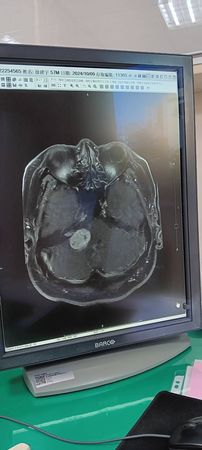

▲徐亨亮出腦瘤位置。(圖/翻攝自FACEBOOK/徐亨-鐵粉團隊-鐵亨團)

徐亨說明,當時醫師為了緊急處理水腦症,先在腦部裝設導流器,並在身體3處植入引流管,將腦內積水排出體外,由於腦瘤位置靠近神經系統,手術風險極高,經過慎重考量後,暫時以放射與藥物療法控制腫瘤。

術後,徐亨經歷長達一年多的復健期才逐漸恢復正常生活,目前因腫瘤壓迫神經,他出現嚴重耳鳴,右耳聽力幾乎喪失,僅剩左耳可聽,只能選擇與病共處。談到外界對他身材變化的關注,他坦言,因長期服藥治療導致賀爾蒙變化,出現「月亮臉」、水腫與體重增加,這些都非單純飲食或生活習慣所致。